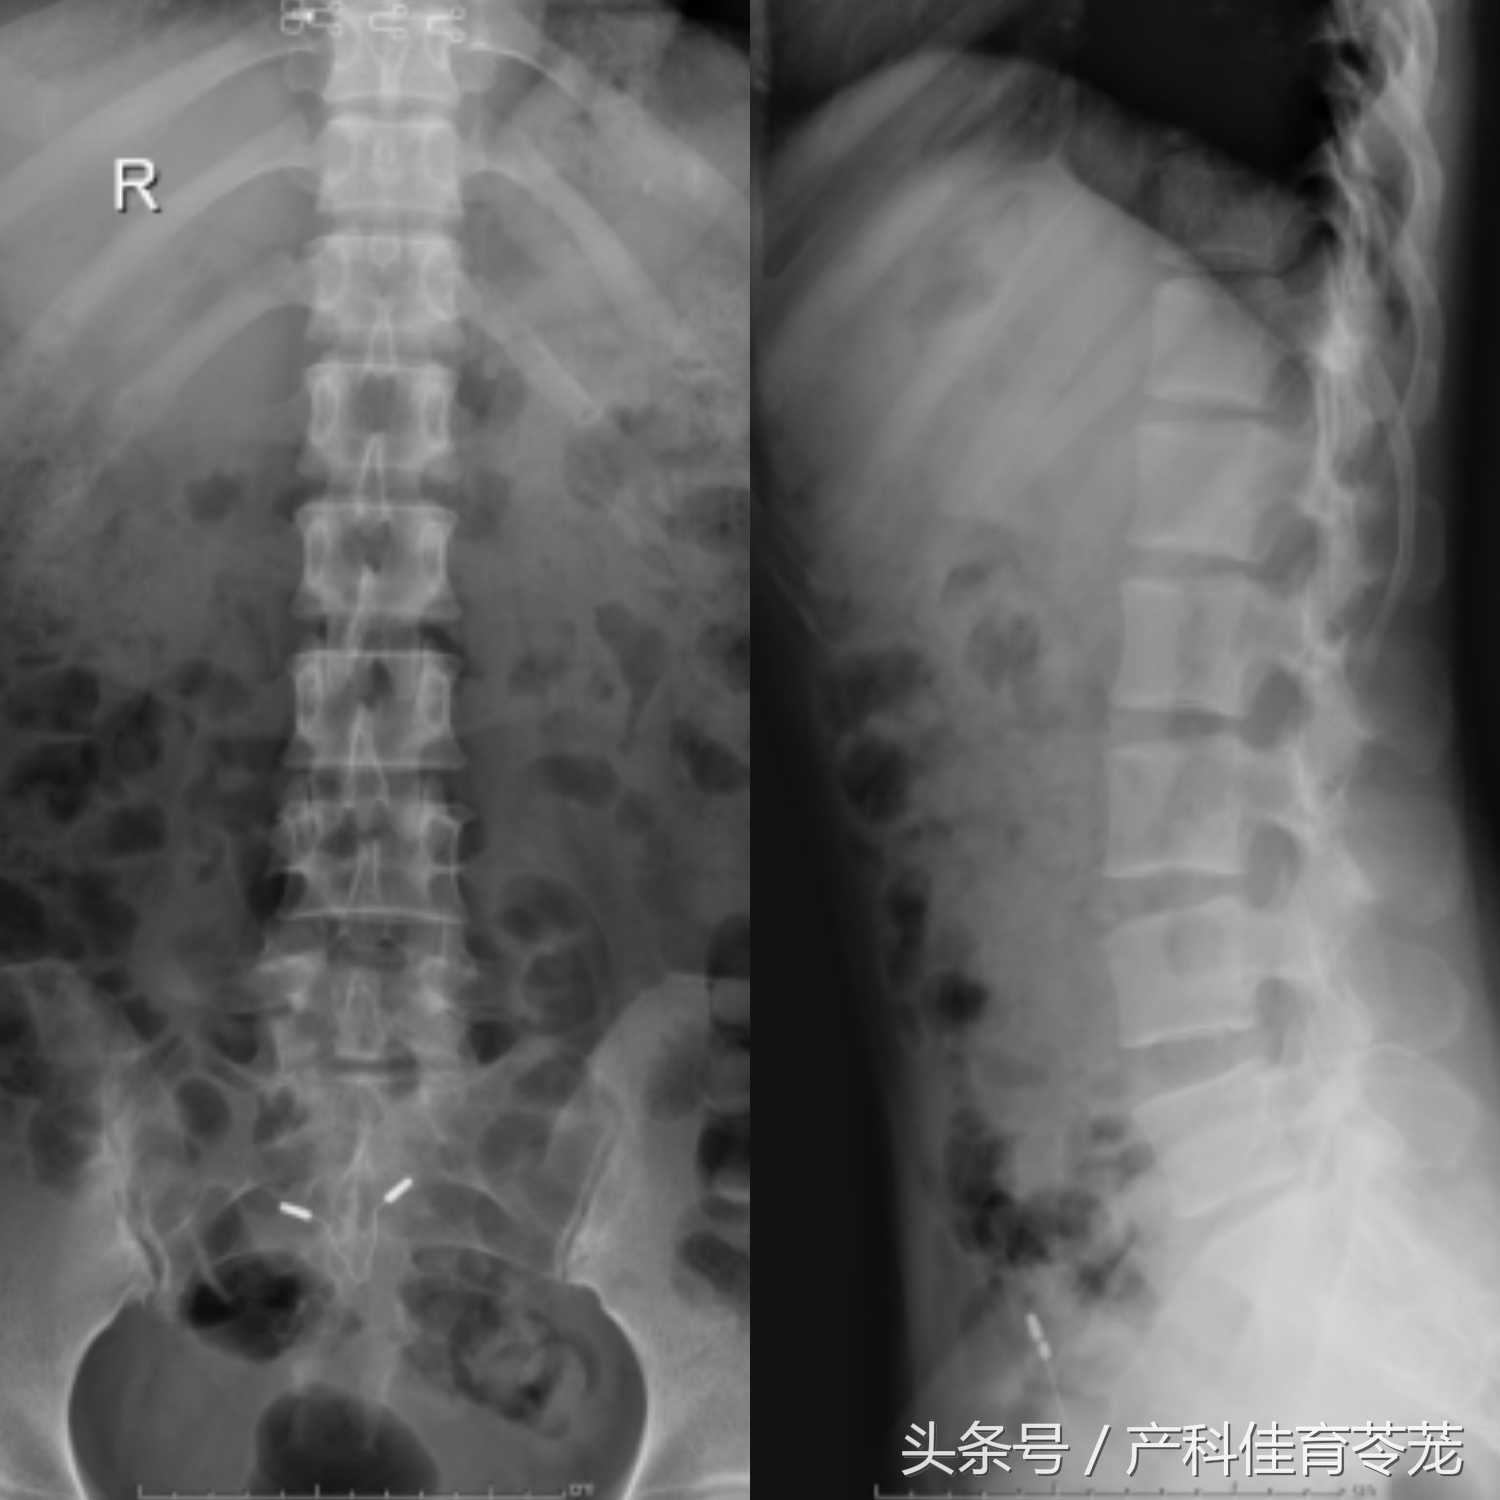

术前腰椎X光片提示:腰5骶1椎间隙明显狭窄,高度降低。